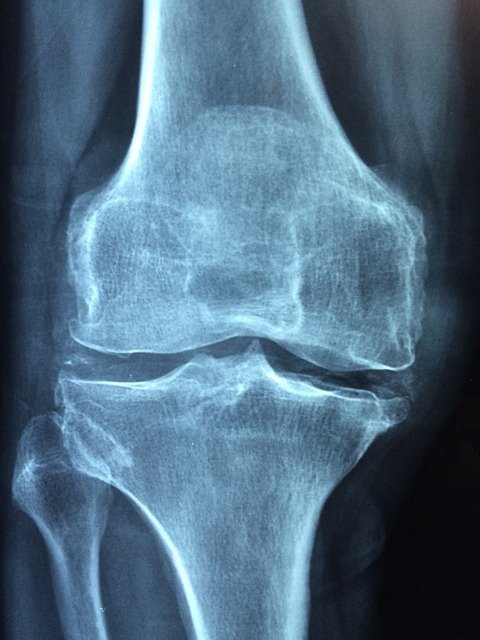

ऑस्टियोआर्थराइटिस (OA) और रयूमेटाइड आर्थराइटिस (RA) में अंतर

ऑस्टियोआर्थराइटिस और रयूमेटाइड आर्थराइटिस में अंतर

ऑस्टियोआर्थराइटिस (Osteoarthritis या OA) और रयूमेटाइड आर्थराइटिस (Rheumatoid Arthritis या RA) में अंतर जानना चाहते हैं तो ये लेख जरूर पढ़ें |